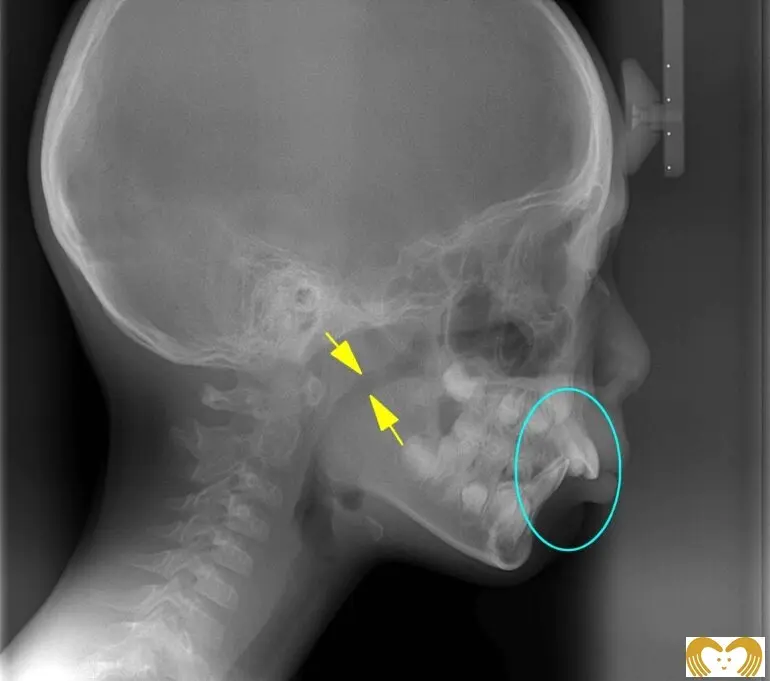

症例03:出っ歯

《Before》《After》

- 年齢:

- 8~12歳

- 性別:

- 男の子

- 治療内容:

- ネオキャップシステムによる、上顎前突(出っ歯)の治療。矯正前後のレントゲン比較から、気道(黄色矢印部分)が広くなっていることがわかります。現在は、当初見られた口呼吸も改善され、自然と鼻呼吸ができるようになりました。

- 治療回数・期間:

- 約4年間

- 治療費:

- 495,000円(税込)

- リスク:

- 取り外し可能な装置の為、治療の効果が使用頻度に左右されます。